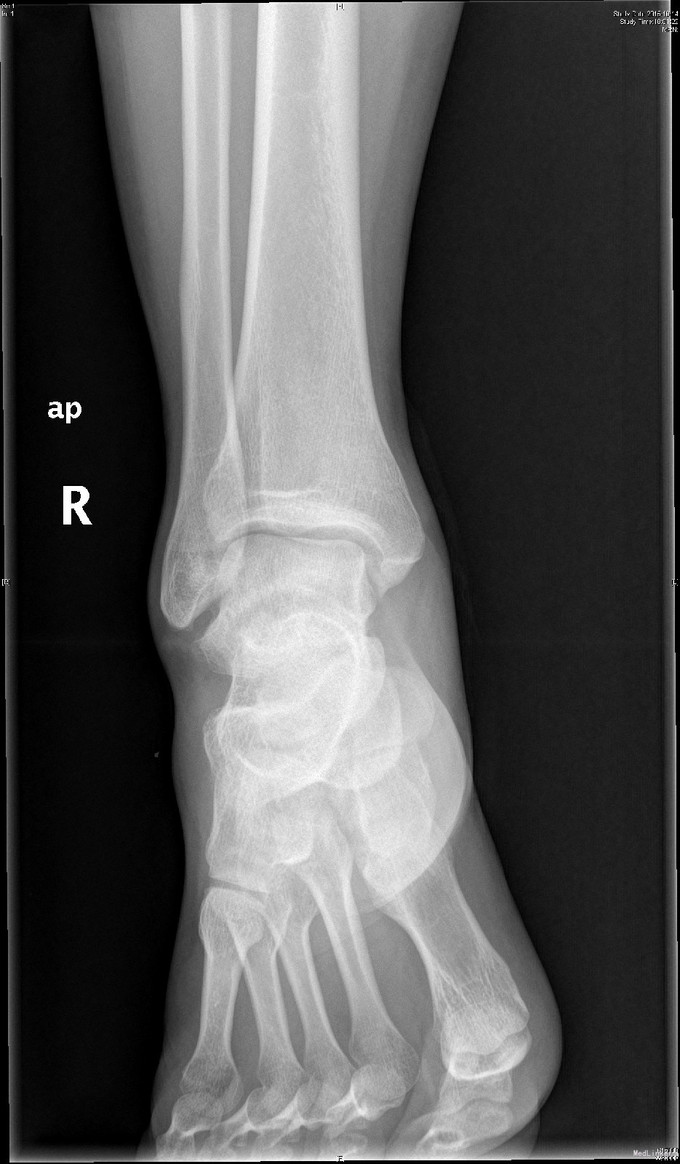

主诉:右踝扭伤后疼痛3年,伴活动受限2年。 现病史:患者男性,24岁。3年前,患者运动时扭伤右踝,无出血。患者当时至外院就诊,予消炎药物保守治疗,疼痛缓解。2年余前患者出现右踝活动受限,以背屈受限明显,伴右踝疼痛,无发热、盗汗,无其它关节痛,无晨僵等。2年来患者自觉右踝疼痛及活动受限症状逐渐加重。外院查MRI示:右胫骨远端前方骨质增生、右距骨前方骨性隆起、右踝关节内积液。我院查右踝X线示:右距骨前下方骨质密度增高、右胫骨前缘骨质增生。于我院就诊,门诊拟"右踝前方撞击综合征、右距骨骨软骨瘤、右踝滑膜炎"收入院。

查体:左下肢、双上肢肌力及活动度正常。右腓肠肌稍萎缩,右踝无明显肿胀。右踝关节跖屈、背屈受限,右踝内侧及前方关节间隙压痛(+)。ADT(-),下蹲提踵试验(+),内翻试验(-)。右腓肠肌肌力、肌张力、感觉正常。 辅查:见现病史。图片见下。

入院诊断:右踝前方撞击综合征、右距骨骨软骨瘤、右踝滑膜炎 治疗:入院完善术前检查后行右踝关节镜下滑膜清理+前方撞击成形+距骨骨软骨瘤切除。